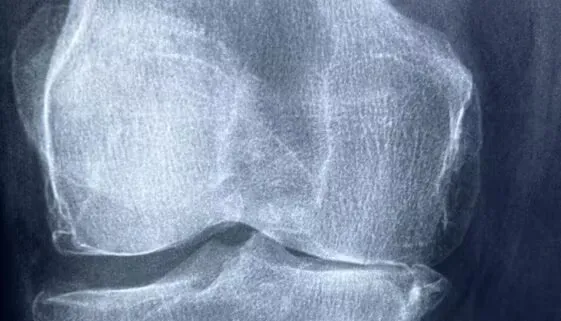

Rekonstrukcja łąkotki to zabieg chirurgiczny mający na celu przywrócenie funkcji stawu kolanowego po uszkodzeniu tej kluczowej struktury. Proces rekonwalescencji po takim zabiegu wymaga nie tylko […]